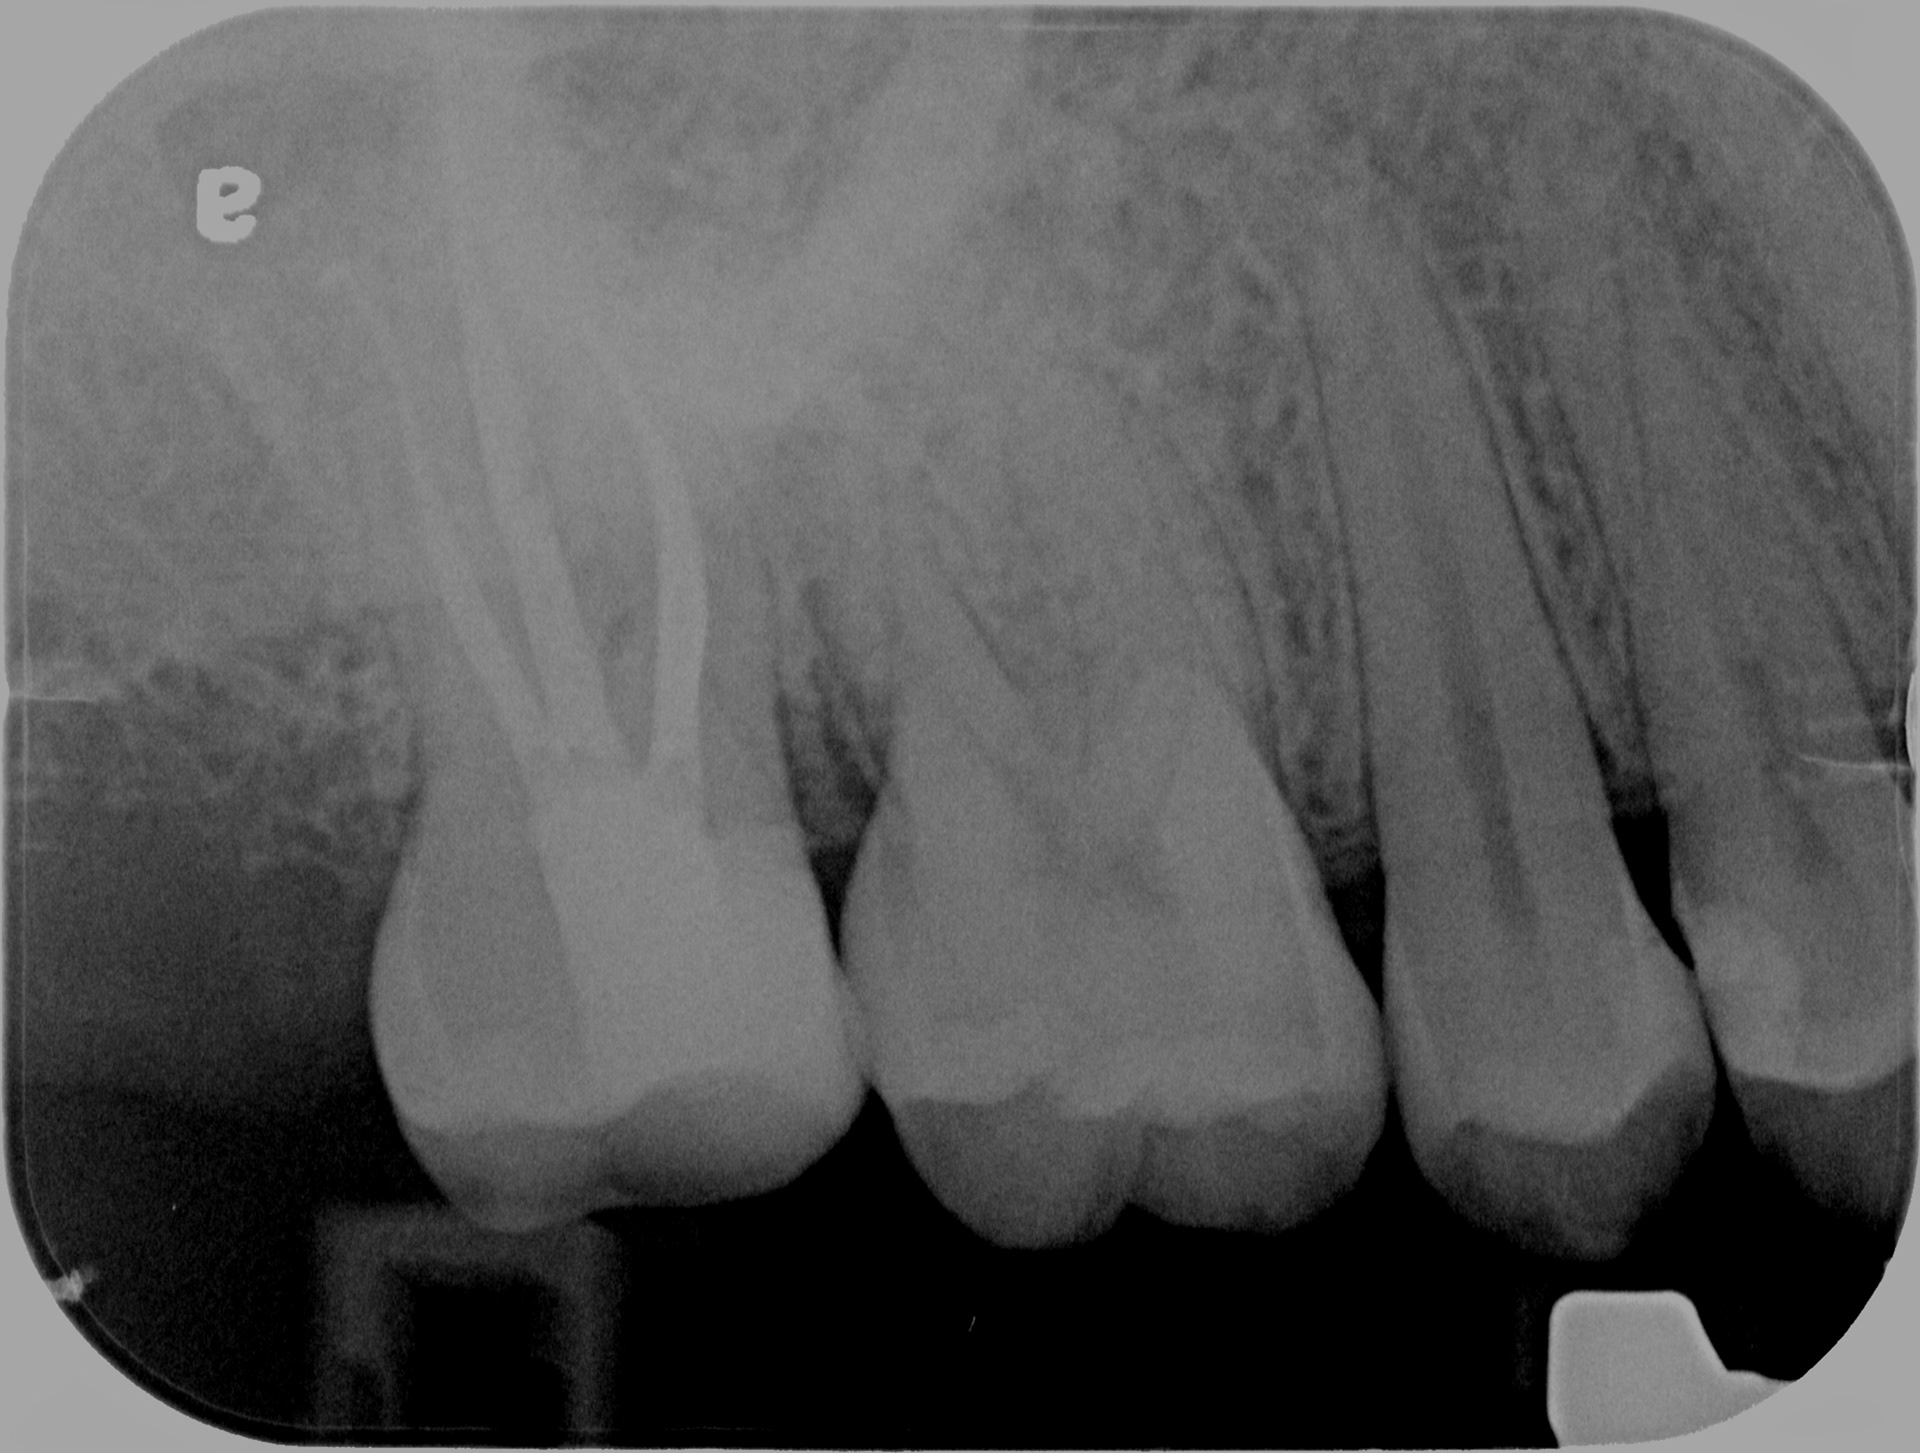

3 MONTHS FOLLOW UP